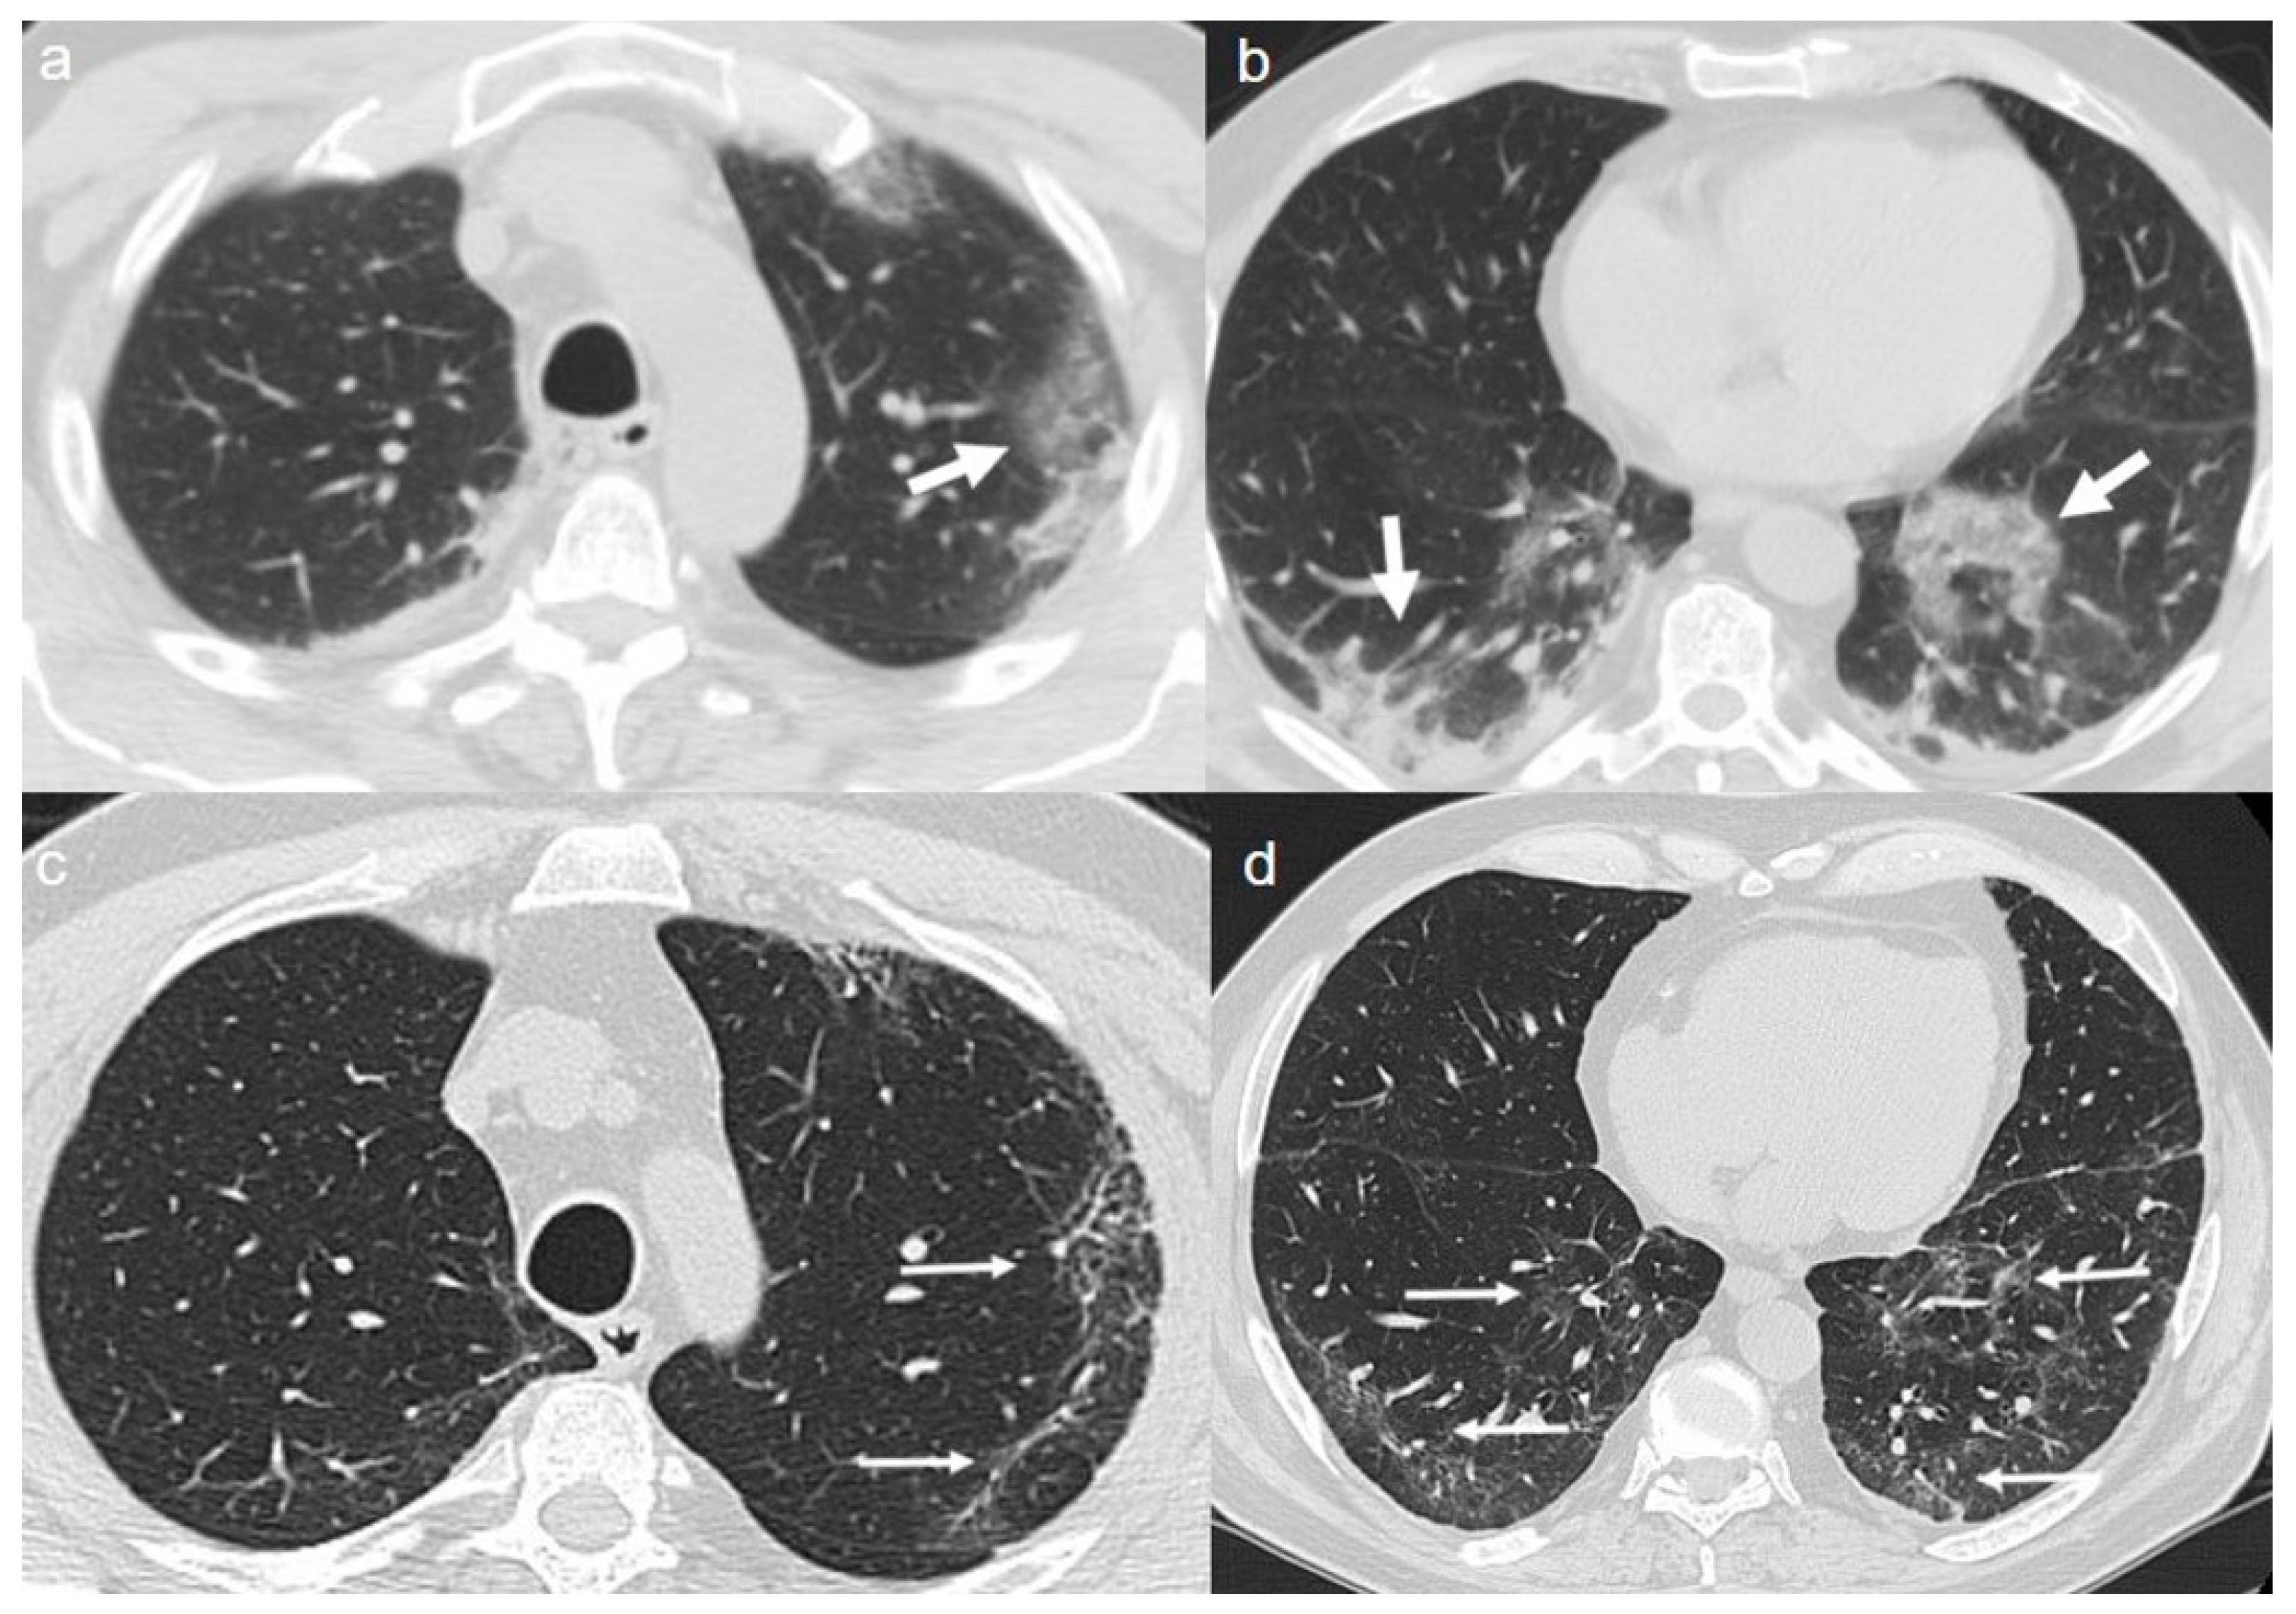

On admission, an unenhanced chest CT showed multiple, rounded ground-glass opacities (GGOs) with peripheral distribution, especially in the right lower lobe (Figure 1a,b).

A chest CT at 4 months from the onset of symptoms showed complete reabsorption of GGOs with no lung abnormalities (Figure 1c,d).

Figure 1. (a,b) CT shows areas of ground-glass opacities (GGO) with peripheral distribution in right lower lobe (arrows). (c,d) CT after 4 months from the onset of symptoms shows complete reabsorption of GGOs with no lung abnormalities.